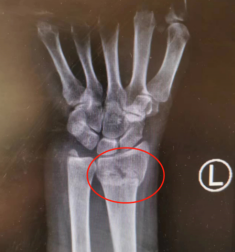

手外科:桡骨远端骨折

手外科滕道练副主任医师介绍,手外科门、急诊接诊的多为桡骨远端骨折患者。

桡骨远端骨折是指桡骨下端关节面3cm以内的骨折。该部位为骨松质和骨密质的交界处,为解剖薄弱处,一旦遭受外力,容易骨折。桡骨远端骨折多继发于低能量损伤,比如摔伤等。中老年妇女和儿童需要警惕桡骨远端骨折。

如何避免桡骨远端骨折?滕医生建议,老年人和小朋友遇到雨雪天最好不出门,如果一定要出门,做好防护。如果不慎摔倒,疼痛比较严重,需要到专科医院就诊。